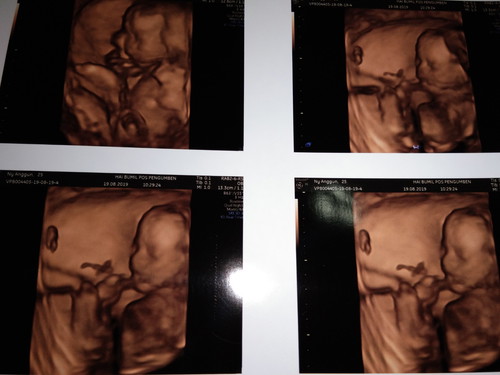

pertama kali lihat wajah dede

20 wekk UsG 4D pertama kali, baru bsa pastiin Jenis kelamin sruh pas 26 week aja katanya huhu lamaaa banget rasanya.. Tapi alhamdulillah sehat yaa de. Smga bunda2 dan dede juga sehat selalu dan lancar sampai persalinan. Aamiin ?